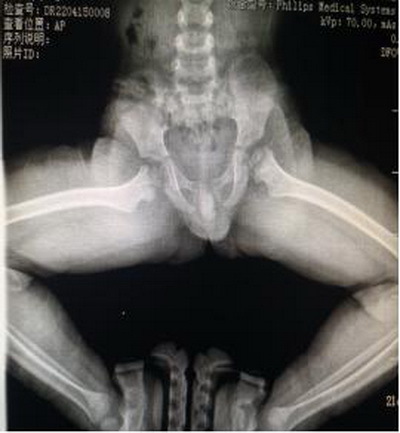

曲敬主任介绍,髋关节内翻畸形就是股骨颈轴线和股骨干轴线之间形成一个内倾角,或称颈干角。正常值在110-140度之间。颈干角大于正常值为髋外翻,小于正常值为髋内翻。先天性髋内翻亦称发育性髋内翻,系幼儿时发生的股骨颈干角进行性减小所致的畸形。正常成人的颈干角为120deg;~140deg;,儿童为135deg;~145deg;。若颈干角小于120deg;,称为髋内翻。表现为日见加重的跛行,是小儿跛行常见原因之一。而患儿PHILIP双侧髋关节颈干角经过曲敬教授团队三维重建后精确测量为左侧108°,右侧104°。

术前双髋关节蛙式位片